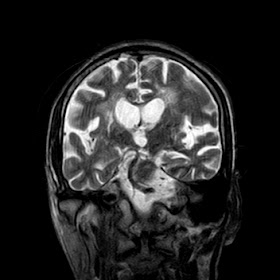

A 55 years old man with....